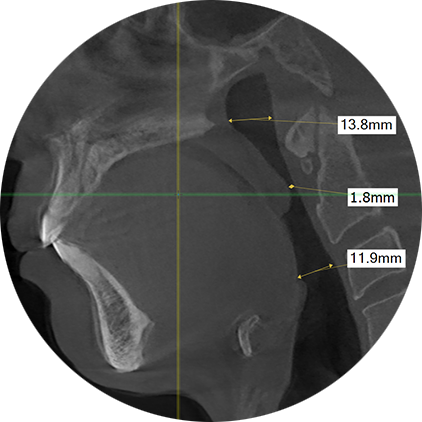

정상인의 기도

남성의 정상적인 기도 크기는 혀 아래쪽으로 12-15mm, 혀 중간 10-12mm 이상 이며, 연구개(목젖) 뒤쪽은 7-10mm 이상 입니다.

체격이 작은 여성의 경우 혀 뒤쪽은10mm 이상 입니다.

재발된 환자 기도

재발된(처음부터 치료가 제대로 되지 않은) 환자들은 치료 후임에도 불구하고

혀 뒤쪽 설근부위의 기도 크기가 대부분 7-10m 이하로, 자로 재지 않아도 10-15mm 이상의 정상인의 기도크기보다 작습니다.

재발된(처음부터 치료가 제대로 되지 않은) 환자들은 치료 후임에도 불구하고 혀 뒤쪽 설근부위의 기도 크기가 대부분 7-10m 이하로, 자로 재지 않아도 10-15mm 이상의 정상인의 기도크기보다 작습니다.